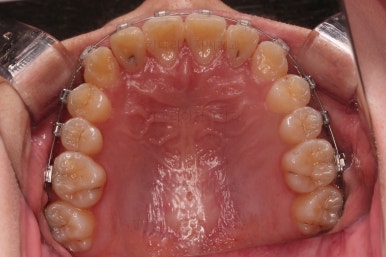

입 안을 보면 밑에 치열이나 다른 부분은 비교적 양호한데 유달리 윗니 송곳니만 위치가 좋지 못하네요.

충치가 곳곳에 보이는데요.

성인들은 충치가 멈춰있는 정지우식일 가능성도 있으며 크기가 현재 크지 않고 향후 변화되지 않는다면 그대로 두기도 합니다.

이번 환자분도 교정치료에 방해되는 부분이나 급해보이는 추료만 우선 진행하고 교정 중에 충치가 커지는지 증상이 생기는지 관찰해 보기로 했습니다.